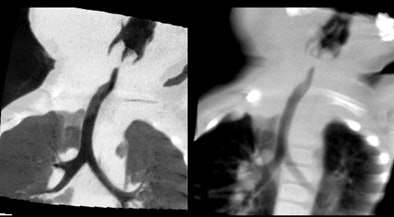

| Feeding artery is visible at 320-detector-row CT in a patient with pulmonary blastoma. |

| Vascular ring and hypothesis of tracheal stenosis. Images at 320-detector-row CT. |